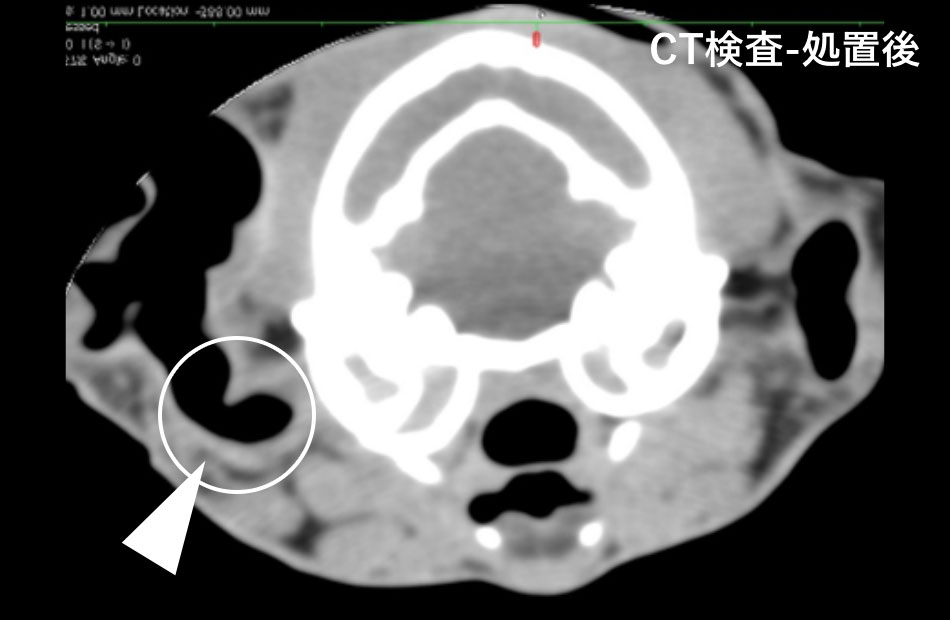

右外耳内は腫瘤による閉塞所見を認めました(図:丸内矢印が腫瘤による閉塞部位)。鼻咽頭部へのポリープは認めませんでした。

内視鏡を用いて、右外耳内の深くにあるポリープを内視鏡鉗子で摘出しました(図:矢印がポリープ、CT検査では丸内矢印の閉塞部位が消失)。その後は、外耳炎症状は消失しました。摘出した腫瘤の診断名は「鼻咽頭ポリープ」でした。右耳道内での再発は認めませんでしたが、8カ月後の反対の左外耳内に同様のポリープが生じ、再度摘出を行いました。